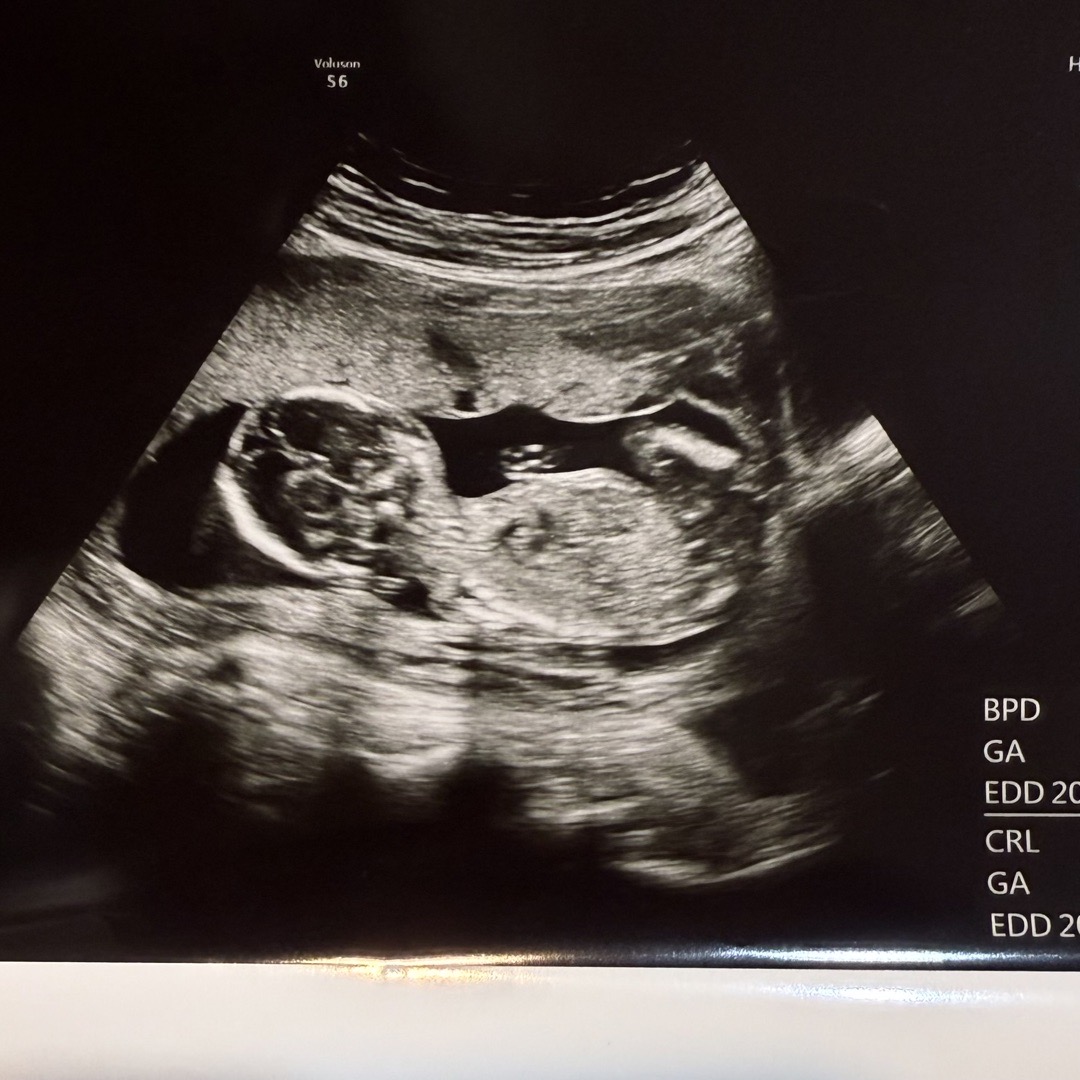

15주차 6일 성별질문 의사쌤도 잘 모르겠데요;;

다른분들은 빠르몈 12-13주에도 알던데 ㅠㅠ 저번주도 모르겟다하시고 오늘도 정확하니 않다거 하시고 빨리 알고싶읔데,,, 한달 뒤에나 오라고 하네요 😭😭 -> 아들입니다!!